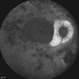

- rubella, congenital rubella, bilateral pigmentary retinopathy

- Bilateral pigmentary retinopathy in a young patient with a history of congenital rubella.